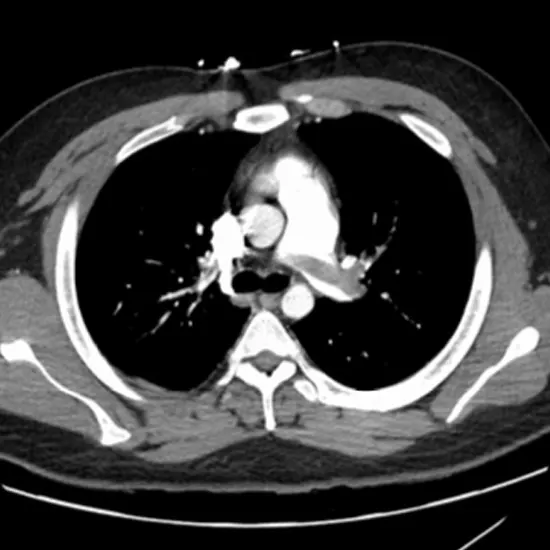

CT (Computed Tomography) Angiography Thoracic is an imaging procedure to diagnose the acute as well as chronic abnormalities of the thoracic aorta. The thoracic aorta abnormalities include aortic aneurysms, aortic dissection, intramural hematoma, penetrating atherosclerotic ulcer, traumatic aortic transection, congenital malformations and many more.

A doctor usually prescribes CT Angiography thoracic to patients with severe chest pain. It is used to diagnose the acute as well as chronic abnormalities of the thoracic aorta such as aortic aneurysms, aortic dissection, intramural hematoma, penetrating atherosclerotic ulcer, traumatic aortic transection, congenital malformations etc.

CT Angiography Thoracic (Computed Tomography) screening of the thoracic is a non-invasive radiology test used to evaluate the thoracic blood vessel abnormalities and surrounding tissue. CT Angiography Thoracic is done to look for the conditions of the thoracic blood vessels and the surrounding area.